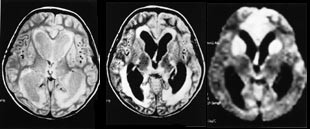

Iskemiske hjerneforandringer avdekkes hos et stort antall pasienter i de høyere aldersgrupper, ofte uten at de relativt iøynefallende MR-funn gir symptomer. Demyelinisering er også ganske lett å fremstille ved en rekke MR-sekvenser, og MR har etter hvert utviklet seg til å bli uunnværlig i diagnostikken av multippel sklerose (15, 16) (fig 5).

Demyelinisering av annen årsak vil også lett kunne demonstreres ved MR , men differensialdiagnostikken mellom sykdommene er ofte vanskelig (16).